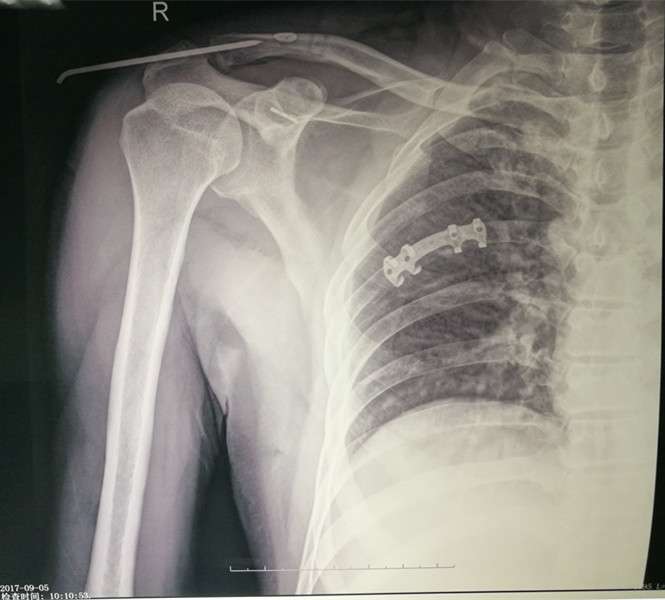

2017年8月22日,我院骨四科燕飞主任医师于肩关节镜下成功完成了一例喙锁韧带重建术治疗肩锁关节脱位,患者男性、47岁,外伤后右肩部疼痛入院,入院后经相关检查,诊断为:右肩锁关节脱位,燕飞主任医师在详细询问病史、进行相关查体后决定行肩关节镜下喙锁韧带重建术治疗肩锁关节脱位,手术过程顺利,术后患者功能恢复良好。现就肩关节镜下喙锁韧带重建术治疗肩锁关节脱位的相关知识介绍如下:

肩锁关节脱位为肩部常见损伤,临床上症状、体征明显,根据 X 线片可基本得到明确诊断。AO锁骨钩钢板是治疗肩锁关节脱位的经典方法,也是基层医院广泛使用的固定方式。但长期随访发现,锁骨钩钢板术后影响肩关节的外展活动,形成肩关节撞击综合征;因应力遮挡产生肩峰下骨质溶解等并发症;同时取出钢板后还可能并发再次脱位的风险。随着微创理念的不断深入以及关节镜技术的快速普及,关节镜技术在肩锁关节脱位的微创治疗中逐渐得到推广,其有效性及安全性不断得到验证。

关节镜辅助或全关节镜下治疗肩锁关节脱位临床疗效得到了认可。Endobutton带袢钢板最初用于膝关节前后交叉韧带的重建。Struhl首次使用Endobutton带袢钢板技术重建喙肩韧带并取得良好的效果。此后逐渐得到推广。在一项长达 11 年的研究结果显示,双 Endobutton 带袢钢板能有效恢复急性和慢性肩锁关节脱位的稳定性,获得良好的临床疗效和影像学表现。

关节镜辅助使用双Endobutton带袢钢板治疗肩锁关节脱位,创伤小,恢复快,有利于损伤的韧带和韧带充分愈合和瘢痕化;通过袢及钢板,在锁骨端和喙突基底形成垂直方向的刚性稳定结构,使锁骨远端足够稳定在解剖位置,使得肩锁、喙锁韧带在肩锁关节稳定的情况下瘢痕愈合;关节镜辅助治疗时还能对肩关节的损伤一并处理;Endobutton 带袢钢板组织相容性好,无需要再次手术取出,减少二次手术带来的创伤和经济负担。